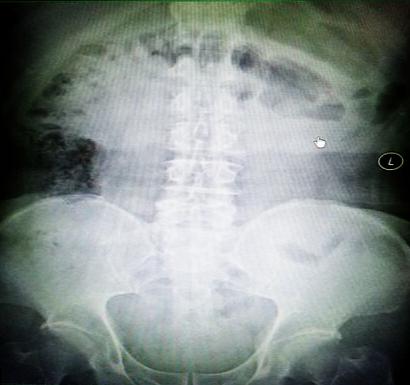

受試患者在結腸端端吻合術中,使用我司新研制產(chǎn)品達到了理想的預期效果。患者術后7天、14天X光片顯影,可降解腸道支架均能按研制設計的預期時間節(jié)點保持應有強度,術后21天X光片顯示可降解腸道支架已完全破碎,并排出體外。在整個試驗過程中,病患無任何不良反映,耐受良好。